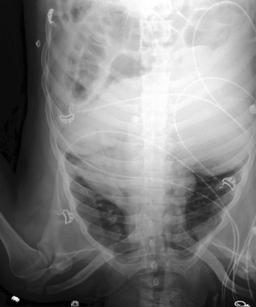

We found that many lateral acquisitions in the dataset were unexpectedly labelled as frontal (Figure 7(a)). Some images contained only noise (Figure 7(b)), non-human samples (Figures 7(d) and 7(e)) or incorrect anatomy (Figure 7(g)). Often, acquisitions with an incomplete field of view (FOV) (i.e., the lungs are not completely visible) were repeated (Figure 7(c)). Lastly, post-processed images were detected by the algorithm such as contrast-enhanced scans (Figure 7(i)) that are not often used for diagnostic purposes in clinical practice.

Curation of imaging datasets

CXR datasets [36] often contain multiple image acquisitions in a single visit due to data quality issues such as a limited field-of-view or scanning the wrong body part (Figure A.7). Unlike [9, 32, 81], we conduct curation to choose higher quality images among the potential candidates instead of performing a random selection. For this step, a separate BioViL-T is trained on ‘clean’ studies with single acquisitions and later used in a zero-shot setting to detect out-of-distribution samples [26, 27] arising from the re-imaging process. The candidate is selected as follows: for a margin . This approach is applied to enhance the quality of the temporal classification dataset given its limited size.